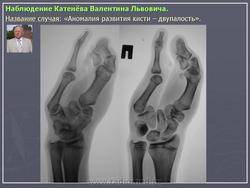

Полидактилия. Полидактилия это врожденная аномалия числа пальцев, которых становится от 6 до 10.Часто встречающаяся полидактилия - раздвоение первого пальца, которое может быть полное, или же раздвоена только ногтевая фаланга. Лечение хирургическое. Аномальные пальцы удаляют

Полидактилия